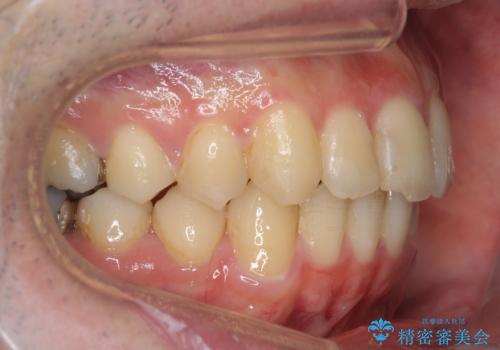

右の歯並びが1本分上が前にずれていました。

本来は抜歯して上の前歯を引っ込めるか、歯を一本分上の奥歯を後ろに下げるやり方が正攻法ですが、

奥歯のかみ合わせを特に変えず、前歯の並びを整える治療をおこないました。

右のかみ合わせを変えず部分矯正にしたことによって、治療が短期間で済み、また、ワイヤーでなくインビザラインで治療が可能、歯も抜かなくて済むなどメリットの多い方法であるといえます。